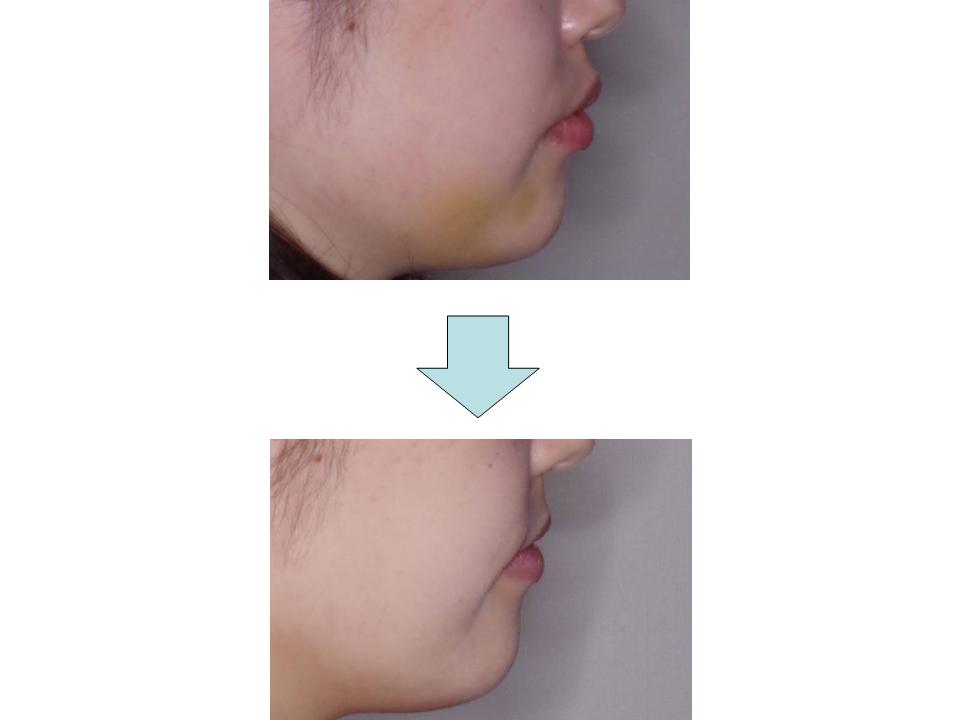

上の前歯が出ている

上の前歯が出ている原因が上下のかみ合わせのズレによるものであるため、上の歯の抜歯を行って前突感の改善を行いました。治療中に妊娠があったためつわりが落ち着いてから装置の撤去を行い、良好なかみ合わせにすることができました。

| 主訴 | 上の前歯が出ている |

| 年齢・性別 | 25歳 / 女性 |

| 抜歯部位 | 上顎両側第一小臼歯、上下顎智歯 |

| 装置 | リンガル(舌側矯正) |

| 期間 | 2年11か月 |